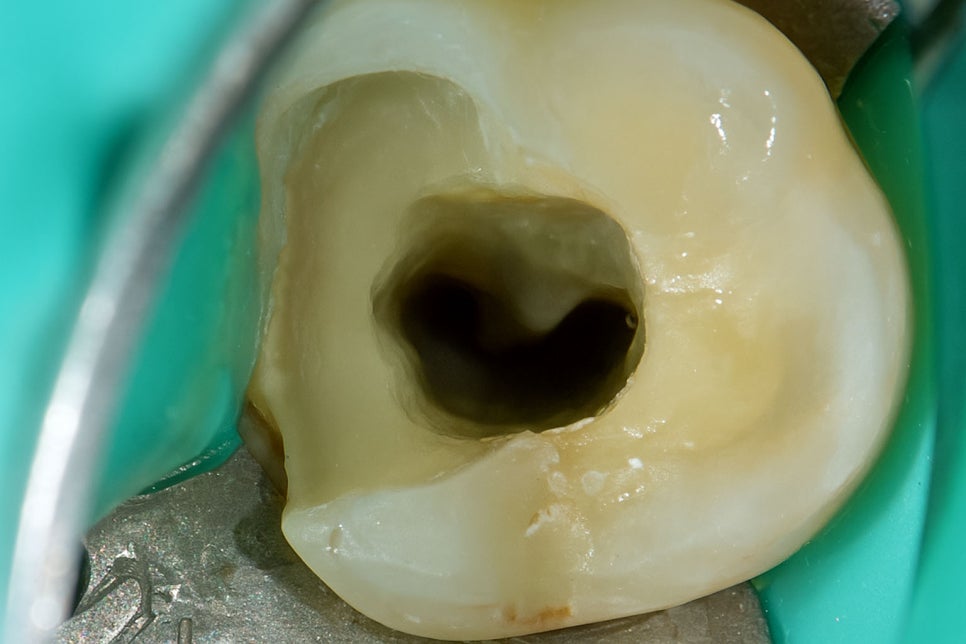

치아 내부에 있는 치수는 복잡한 구조로 되어 있으며

각각의 형태와 구조가 다른 만큼 기형관도 많습니다.

미세현미경은 이렇게 복잡한 구조로 되어있거나

여러 갈래로 갈라져 있는 근관을 찾고

청소하는 과정에서 사용합니다.

가느다란 근관 입구를 맨눈으로는 찾기 어려우나

확대된 시야에서는 명확하게 구분할 수 있게 됩니다.